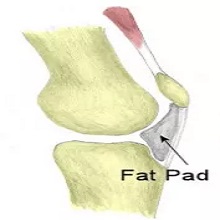

| Једна од веома честих болести колена у општој популацији је остеоартритис. То је хронична болест дегенеративне природе тј. последица је измена у ткивима која сачињавају зглоб, а које настају процесом старења организма. Остеоартритис није специфичан за одређене зглобове, већ може захватити било који. Када је зглоб колена захваћен, то се назива гонартроза. |

Представља један од најчешћих разлога болне осетљивости рамена. У немедицинским круговима често се описује као „укљештење“ мишића у раменом појасу или „сударање мишића и кости“ у пределу рамена. |